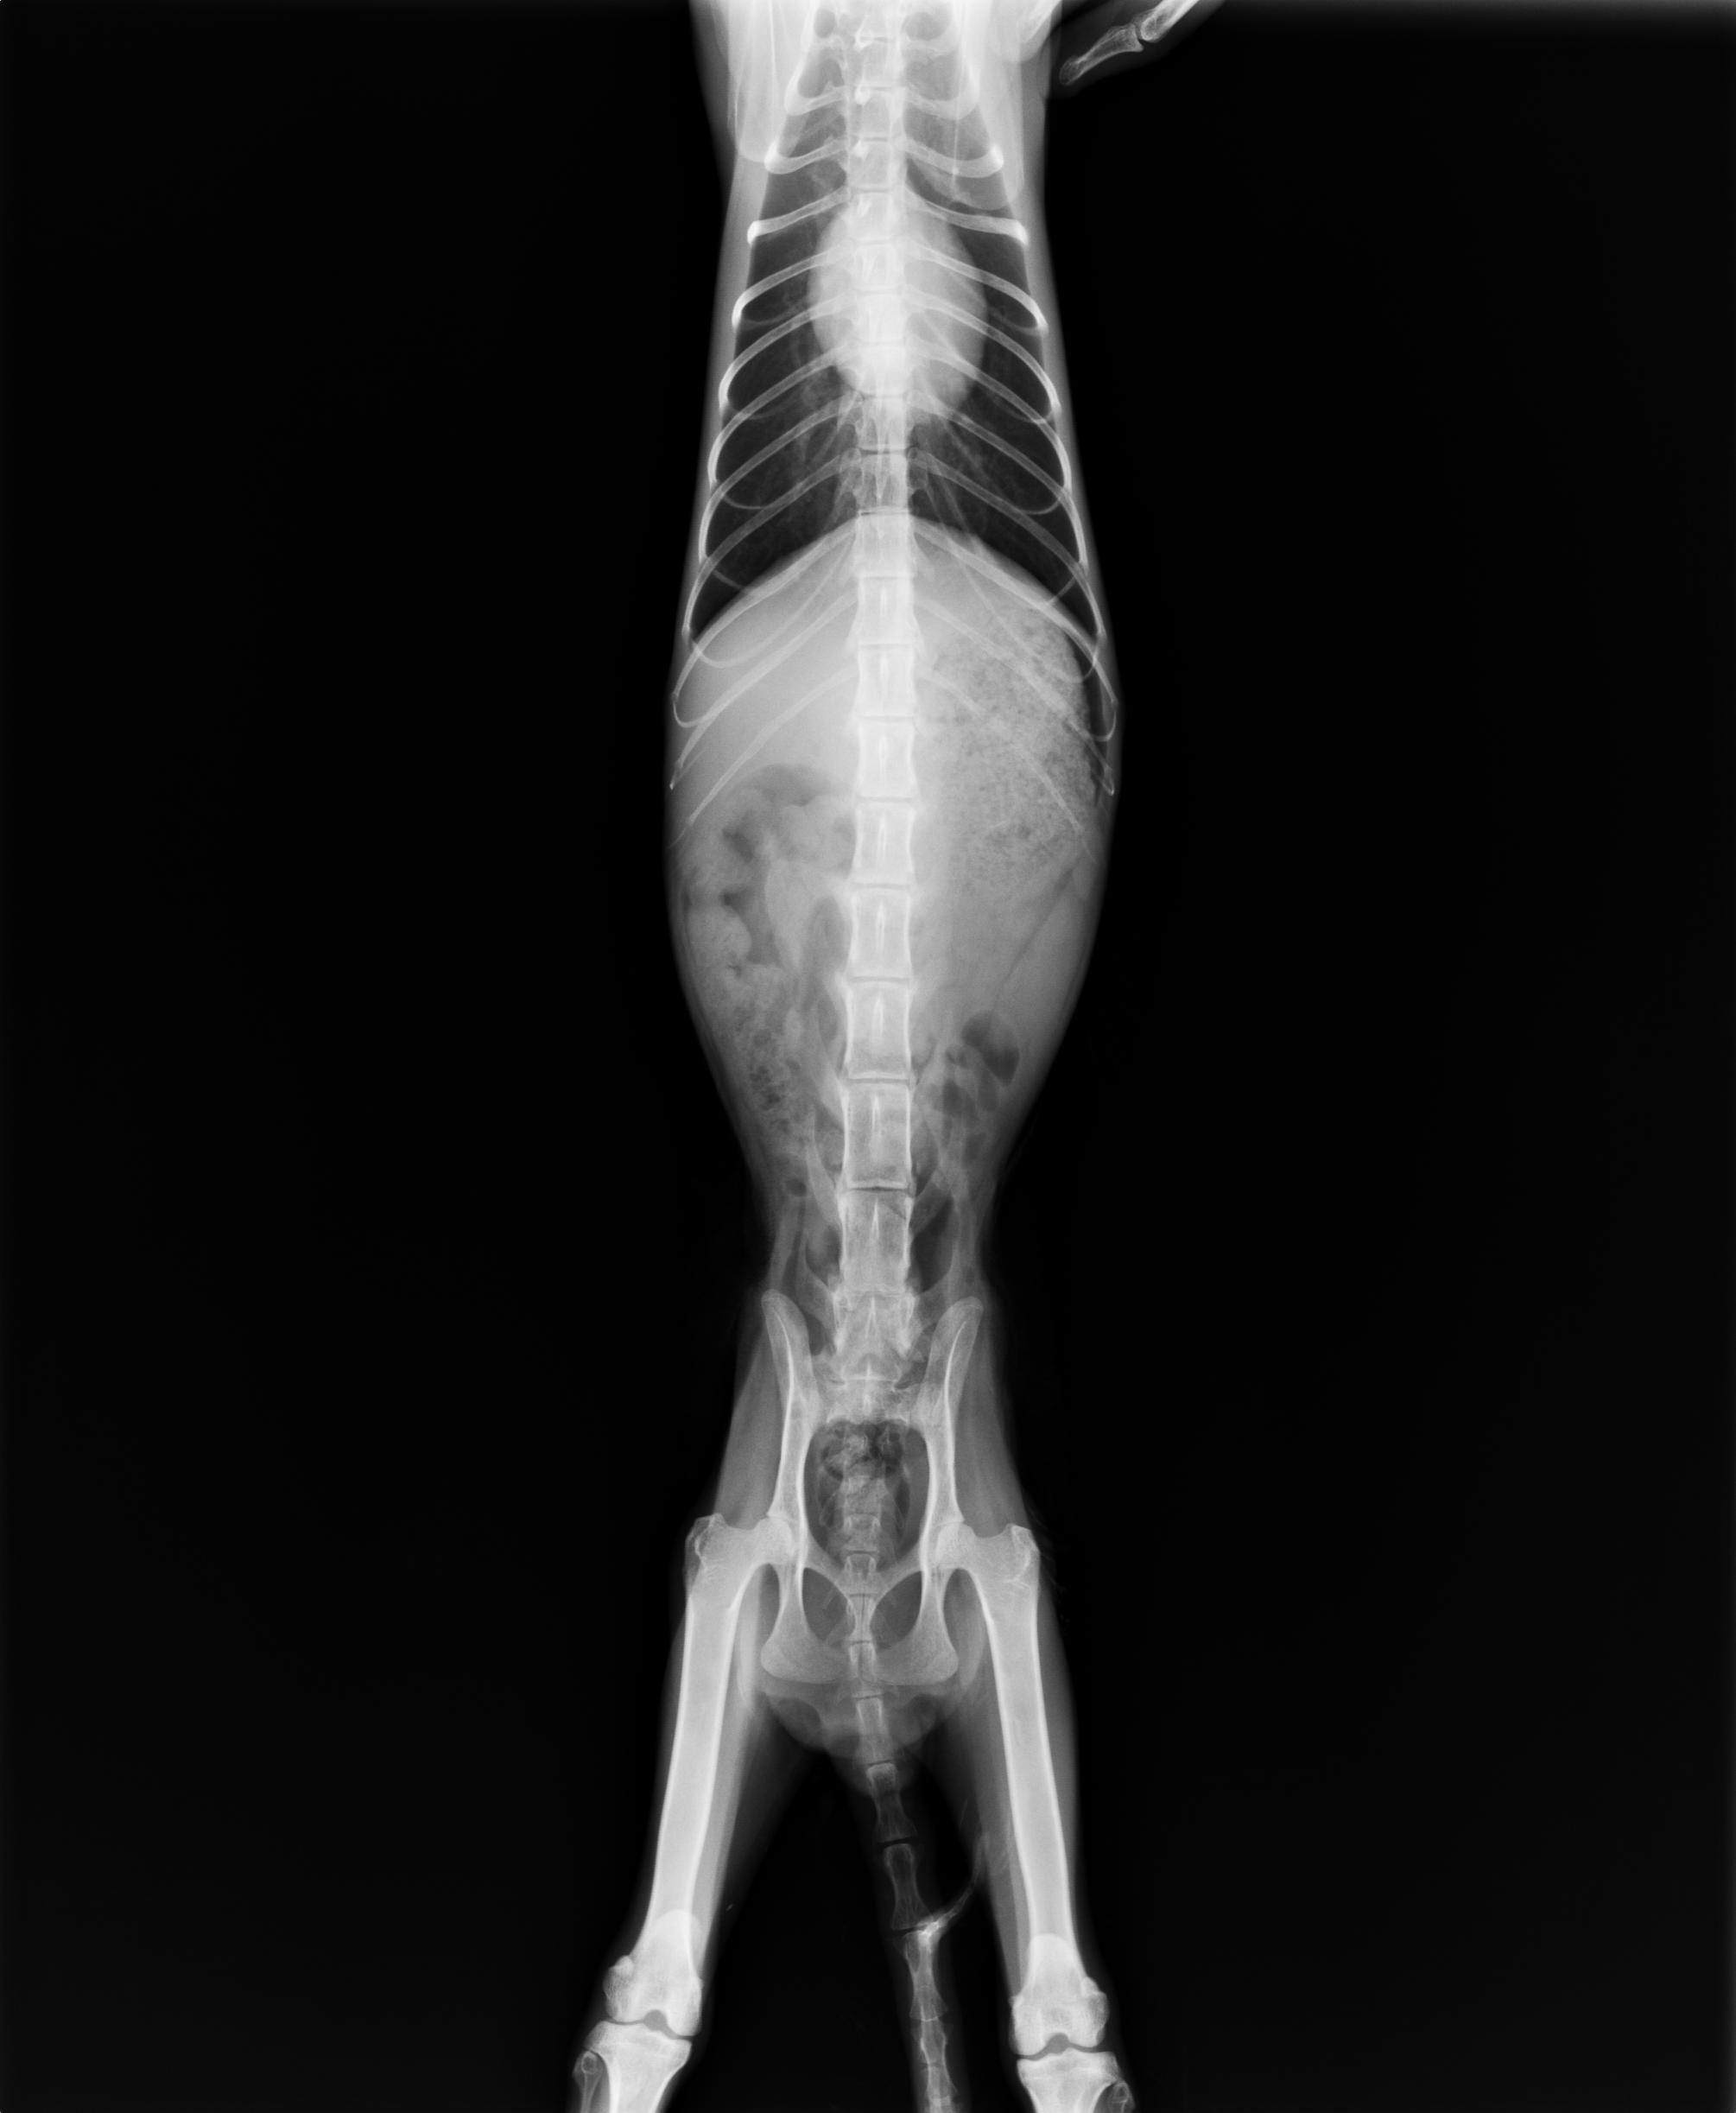

主題: 無法用後腳行走的白白 申請者姓名: Anna Wang 花色: 申請日期: 2012-11-19 23:13:38 申請者部落格: 申請者臉書網址: 所在縣市/合作醫院: 台中市/春天動物醫院 治療費用: 7500元 需求人數: 9人 已結案 (2013-06-27 14:05:53) 報名人員: Katty(已付款)、Weili Chang(已付款)、豆漿(已付款)、Sky(已付款)、Sky(已付款)、Sky(已付款)、Sky(已付款)、Sky(已付款)、Sky(已付款)、 候補人員: 動物病情說明: 11.9被人發現後腿無法行走用拖行的

11.13晚上送至台中春天動物醫院

立即照X光片檢查,脊椎無異!

看傷口的傷勢應該是被狗狗咬傷的~很深膿很多

第一天先清創傷口與抽膿。

醫生明天會做血檢後再評估如何診治及費用。

原則上先住院三天觀察。

11.14

白血球WBC 正常值應該為16900(16.9*1000) 現在測出來為96200(96.2*1000)

診斷為敗血症及嚴重貧血.今天早上體溫已經正常了,食慾正常

目前在打點滴及第二線抗生素及造血針.預估尚須5-6天

11.16

白血球數量由原來的 96200 降為 37700 ,距離正常值16900 已經很接近了

貧血有改善 ,血容比由原先9% 回升到 11%

後半身的傷口已經乾燥了

畢竟是街貓,現在已經恢復會兇的本性了

11.19

白白有再作檢查,白血球數值從37700降為27000,貧血從11%回升到15%,目前會吃乾糧,但是不愛喝水,還是有打營養針。

目前白白已出院,雖然已經可以稍稍行走

但是仍然需要一點時間才能慢慢恢愎

所以先中途,之後可以正常行走跑跳會原地放回。